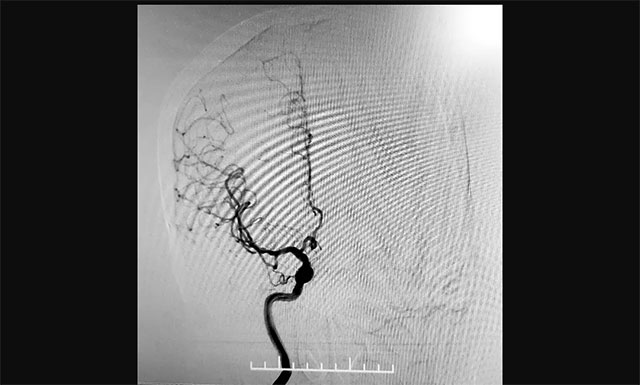

▲ 與傳統(tǒng)經(jīng)股動(dòng)脈穿刺腦血管造影相比,經(jīng)橈動(dòng)脈穿刺造影相對(duì)復(fù)雜,但手術(shù)創(chuàng)傷小、穿刺點(diǎn)血腫發(fā)生率較低

考慮到患者年齡較大,不適宜長時(shí)間臥床,張琪博士遂決定經(jīng)橈動(dòng)脈入路行全腦血管造影術(shù)。經(jīng)過詳細(xì)的術(shù)前準(zhǔn)備,2020年12月26日,張琪博士帶領(lǐng)介入團(tuán)隊(duì)成功為患者進(jìn)行了手術(shù),術(shù)程順利,耗時(shí)約30分鐘,術(shù)后予橈動(dòng)脈壓迫器壓迫術(shù)口,術(shù)后護(hù)理簡(jiǎn)單,不影響康復(fù)治療,無術(shù)后制動(dòng),獲得病人及家屬的一致好評(píng)。